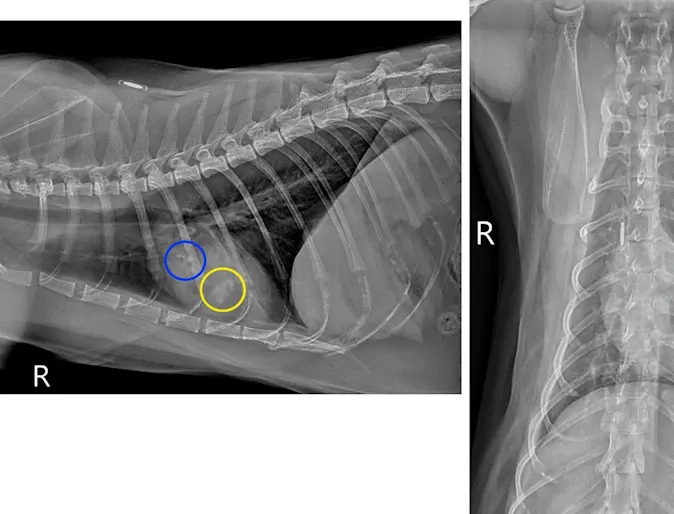

Cardiac Changes and Congestive Heart Failure Secondary to Chagas Disease

Diagnostic Imaging

The patient presented to GCVS Internal Medicine Service for evaluation of ascites.